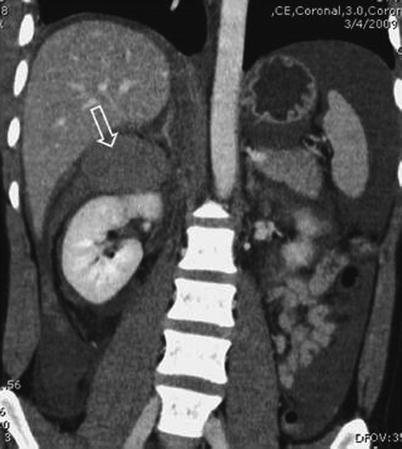

Fig. 20.1

(a) Grade IV right kidney injury with retroperitoneal hematoma (zone II) after multiple gunshot injuries to the back. IV contrast-enhanced CT scan of the abdomen is highly sensitive in diagnosing parenchymal injuries to the kidneys as well as in detecting active extravasation and associated intra-abdominal injuries. (b) Early contrast-enhanced abdominal CT scan after stab wound to the left flank. There is no contrast enhancement of the left kidney due to a renal arterial lesion

Initially, an early phase intravenous contrast CT scan of the abdomen and pelvis is performed. This investigation is highly sensitive in diagnosing parenchymal or vascular injuries to the kidneys as well as in detecting associated injuries (Fig. 20.1). To fully evaluate the collection system, a second CT scan is performed, approximately 10 min after intravenous contrast injection. This technique is known as CT intravenous pyelography (CT-IVP). These delayed-phase images are highly sensitive in diagnosing parenchymal injuries and proximal urine leaks or urinomas and in confirming bilateral functional renal moieties (Fig. 20.2). However, with a low sensitivity of 37 % to detect subtle ureteral injuries, small leaks at this location might be missed. Nevertheless, failure of the distal ureter to opacify on a contrast-enhanced CT scan should raise concern of an injury and should lead to further investigations or intraoperative evaluation of the affected ureter.